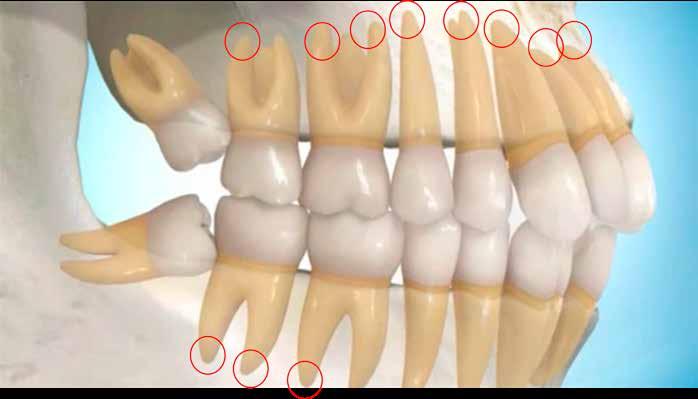

A 19 éves hölgypáciens azzal a kéréssel jelentkezett a rendelőnkbe, hogy szebb fogakat szeretne. Az első konzultáció alkalmával megkérdeztük, hogy mi zavarja leginkább a fogazatának jelenlegi megjelenésében, valamint azt is megbeszéltük vele, hogy milyen végeredmény elérése esetén lenne maradéktalanul elégedett. Ebben az esetben a kezelési célokat az alábbiakban határoztuk meg:

A páciens fogazata esztétikai megjelenésének és funkcionális működésének a lehető legtöbb, saját foganyag megtartása mellett történő helyreállítása (1. és 3. ábra). A lehető legideálisabb esztétikai végeredmény elérése érdekében néhány esetben a fogak alakjának módosítá -

sára is szükség van (2. és 4. ábra).

A kezelés megtervezése során kifejezett jelentősége van annak, hogy jó kommunikáció legyen a páciens, a fogorvos és a fogtechnikus között. A páciens leendő fogazatának természetes megjelenését a kezelésben részt vevő team szakmai felkészültsége, gyakorlati tapasztalata és a kezelés sikerességének irányába történő elkötelezettsége biztosítja. A beavatkozások megkezdése előtt megtörtént a páciens anamnézisének a felvétele, valamint a klinikai kivizsgálását is elvégeztük. Ezt követően lenyomatokat készítettünk a kiindulási állapotról, majd a kiindulási helyzetet extra- és intraorális fotók segítségével is rögzítettük (13. a-c. ábra).